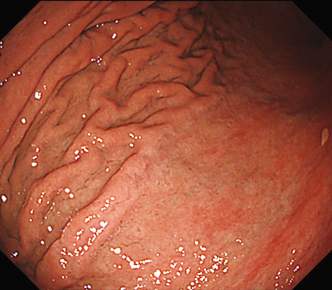

EVIS LUCERA ELITE × GIF1200N 症例画像

遠景部分において明るい視野が確保できる(病変の例)

遠景部分において明るい視野が確保できる(血管の例)

遠景部分において明るい視野が得られ、詳細な粘膜模様の観察が出来る範囲が広い

詳細な粘膜模様の観察範囲向上に貢献する

遠景まで明るく粘膜模様の観察に貢献する

遠景での粘膜模様の観察に貢献する